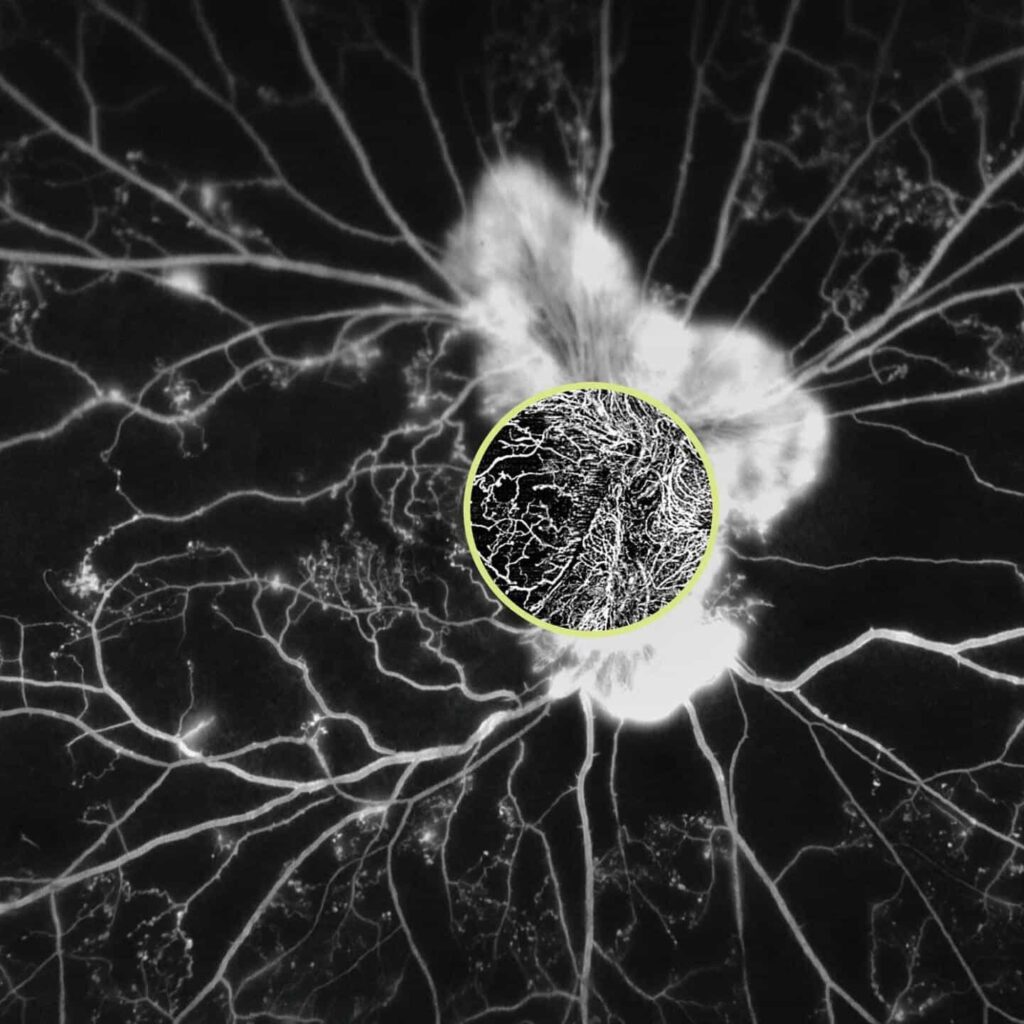

The device now offers wider and deeper OCT/OCTA scans. It features 12 mm × 12 mm OCT angiography and a B-scan depth of up to 2.9 mm. The release said the HD AngioPlex scan provides more detail than previous models.

- High-Definition Imaging: HD OCT and OCT Angiography (OCTA) capture the finest microvascular details of the retina. The CIRRUS 6000 shows the detailed structures and problems of the retina, which is important for good patient care.

- Revolutionary, Yet Routine: The ZEISS AngioPlex® OCT Angiography technology improves how we manage glaucoma and retinal diseases. It offers non-invasive imaging of the tiny blood vessels in the retina. With CIRRUS 6000, revolutionary eye care becomes routine.

AngioPlex® OCT Angiography from ZEISS ushers in a new era of eye care with noninvasive imaging of retinal microvasculature, taking glaucoma and retinal disease management and treatment planning to the next level. By offering the industry’s most comprehensive tools for assessing and analyzing a range of pathologies, ZEISS provides a complete OCT Angiography (OCTA) solution.